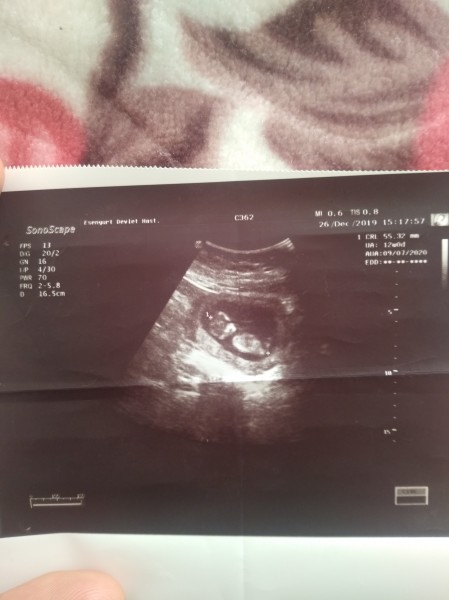

Ultrason Resminden Kac Haftalik Kac Gram Kac Santim Boyu Anlayan Varsa Yardimci Olurmusunuz Guzel Anneler Hamilelik Donemi Genel